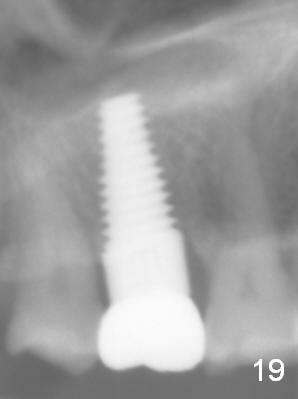

The patient returns for unknown pain on the right side 1.5 years post cementation (Fig.18,19). The gingiva is healthy. Two months later, the tooth #3 is found to have fractured.